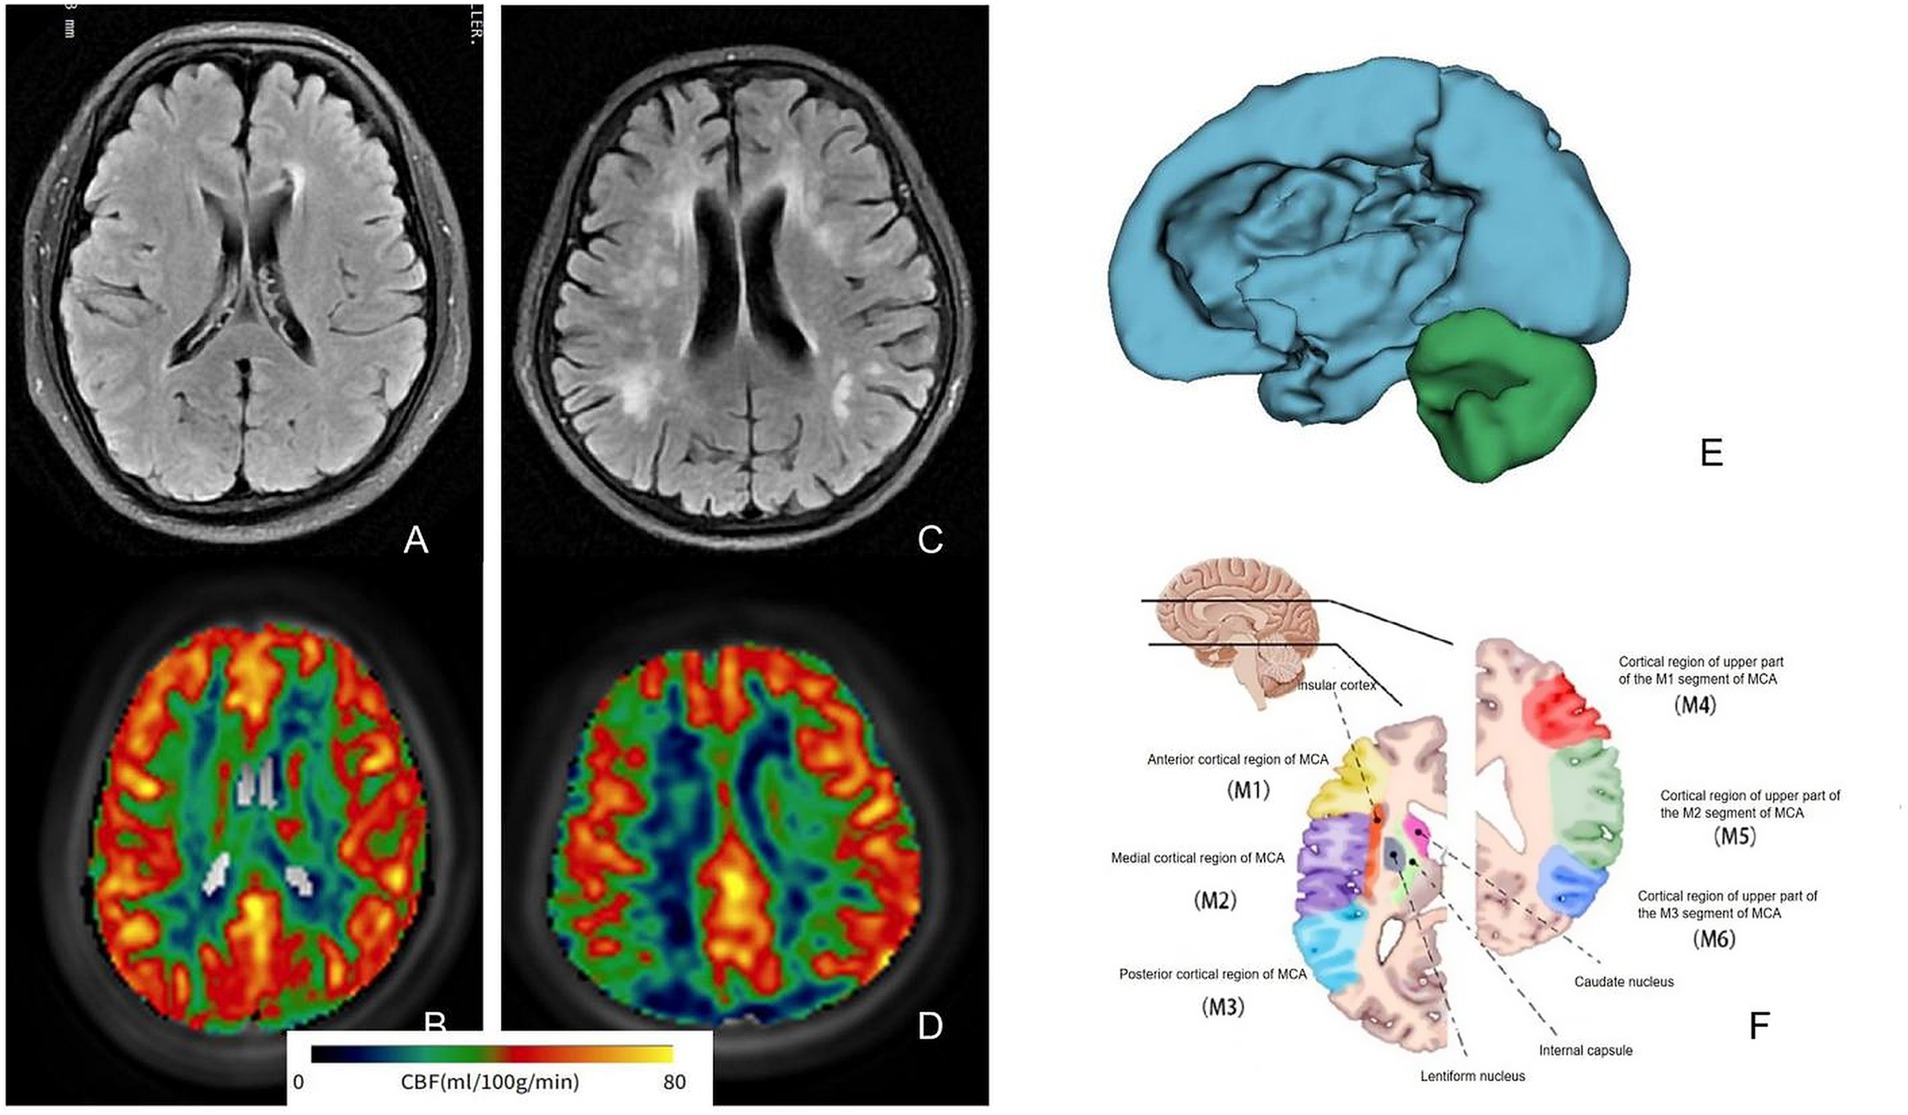

WM region markers were extracted and segmented following the registration of all raw T1WI data to a standard brain segmentation template using CerebralFlow, resulting in 48 anatomical regions. CBF was calculated for PLDs of 1.5 s and 2.5 s to align with the ASL data, with corrected CBF (corr-CBF) derived through appropriate adjustments (refer to Figure 2 for typical examples and registration). Perfusion in the CC was analyzed for both groups, yielding values of 35.84 ± 6.34 mL/(min·100 g) in the mild group and 31.73 ± 8.60 mL/(min·100 g) in the severe group. Additionally, CBF values in the column and fornix were 40.59 ± 8.83 mL/(min·100 g) and 34.28 ± 7.12 mL/(min·100 g), respectively, with p-values of 0.037 and 0.01. No significant differences were observed in perfusion across the other brain regions (p > 0.05; Table 2). Given that this study explored and compared multiple brain regions, the results should be regarded as preliminary findings. Further studies with larger sample sizes are needed to verify these results.

Figure 2

Magnetic resonance analysis of typical WMLs patients shows that (A,B) are FLAIR images and related pseudo-color images of mild patients, and (C,D) are related image data of severe patients. It can be seen that the perfusion of severe patients is relatively low. (E) Shows the process of brain region extraction, and (F) is the schematic image of brain region segmentation at this level. WMLs, white matter lesions; MCA, middle cerebral artery.